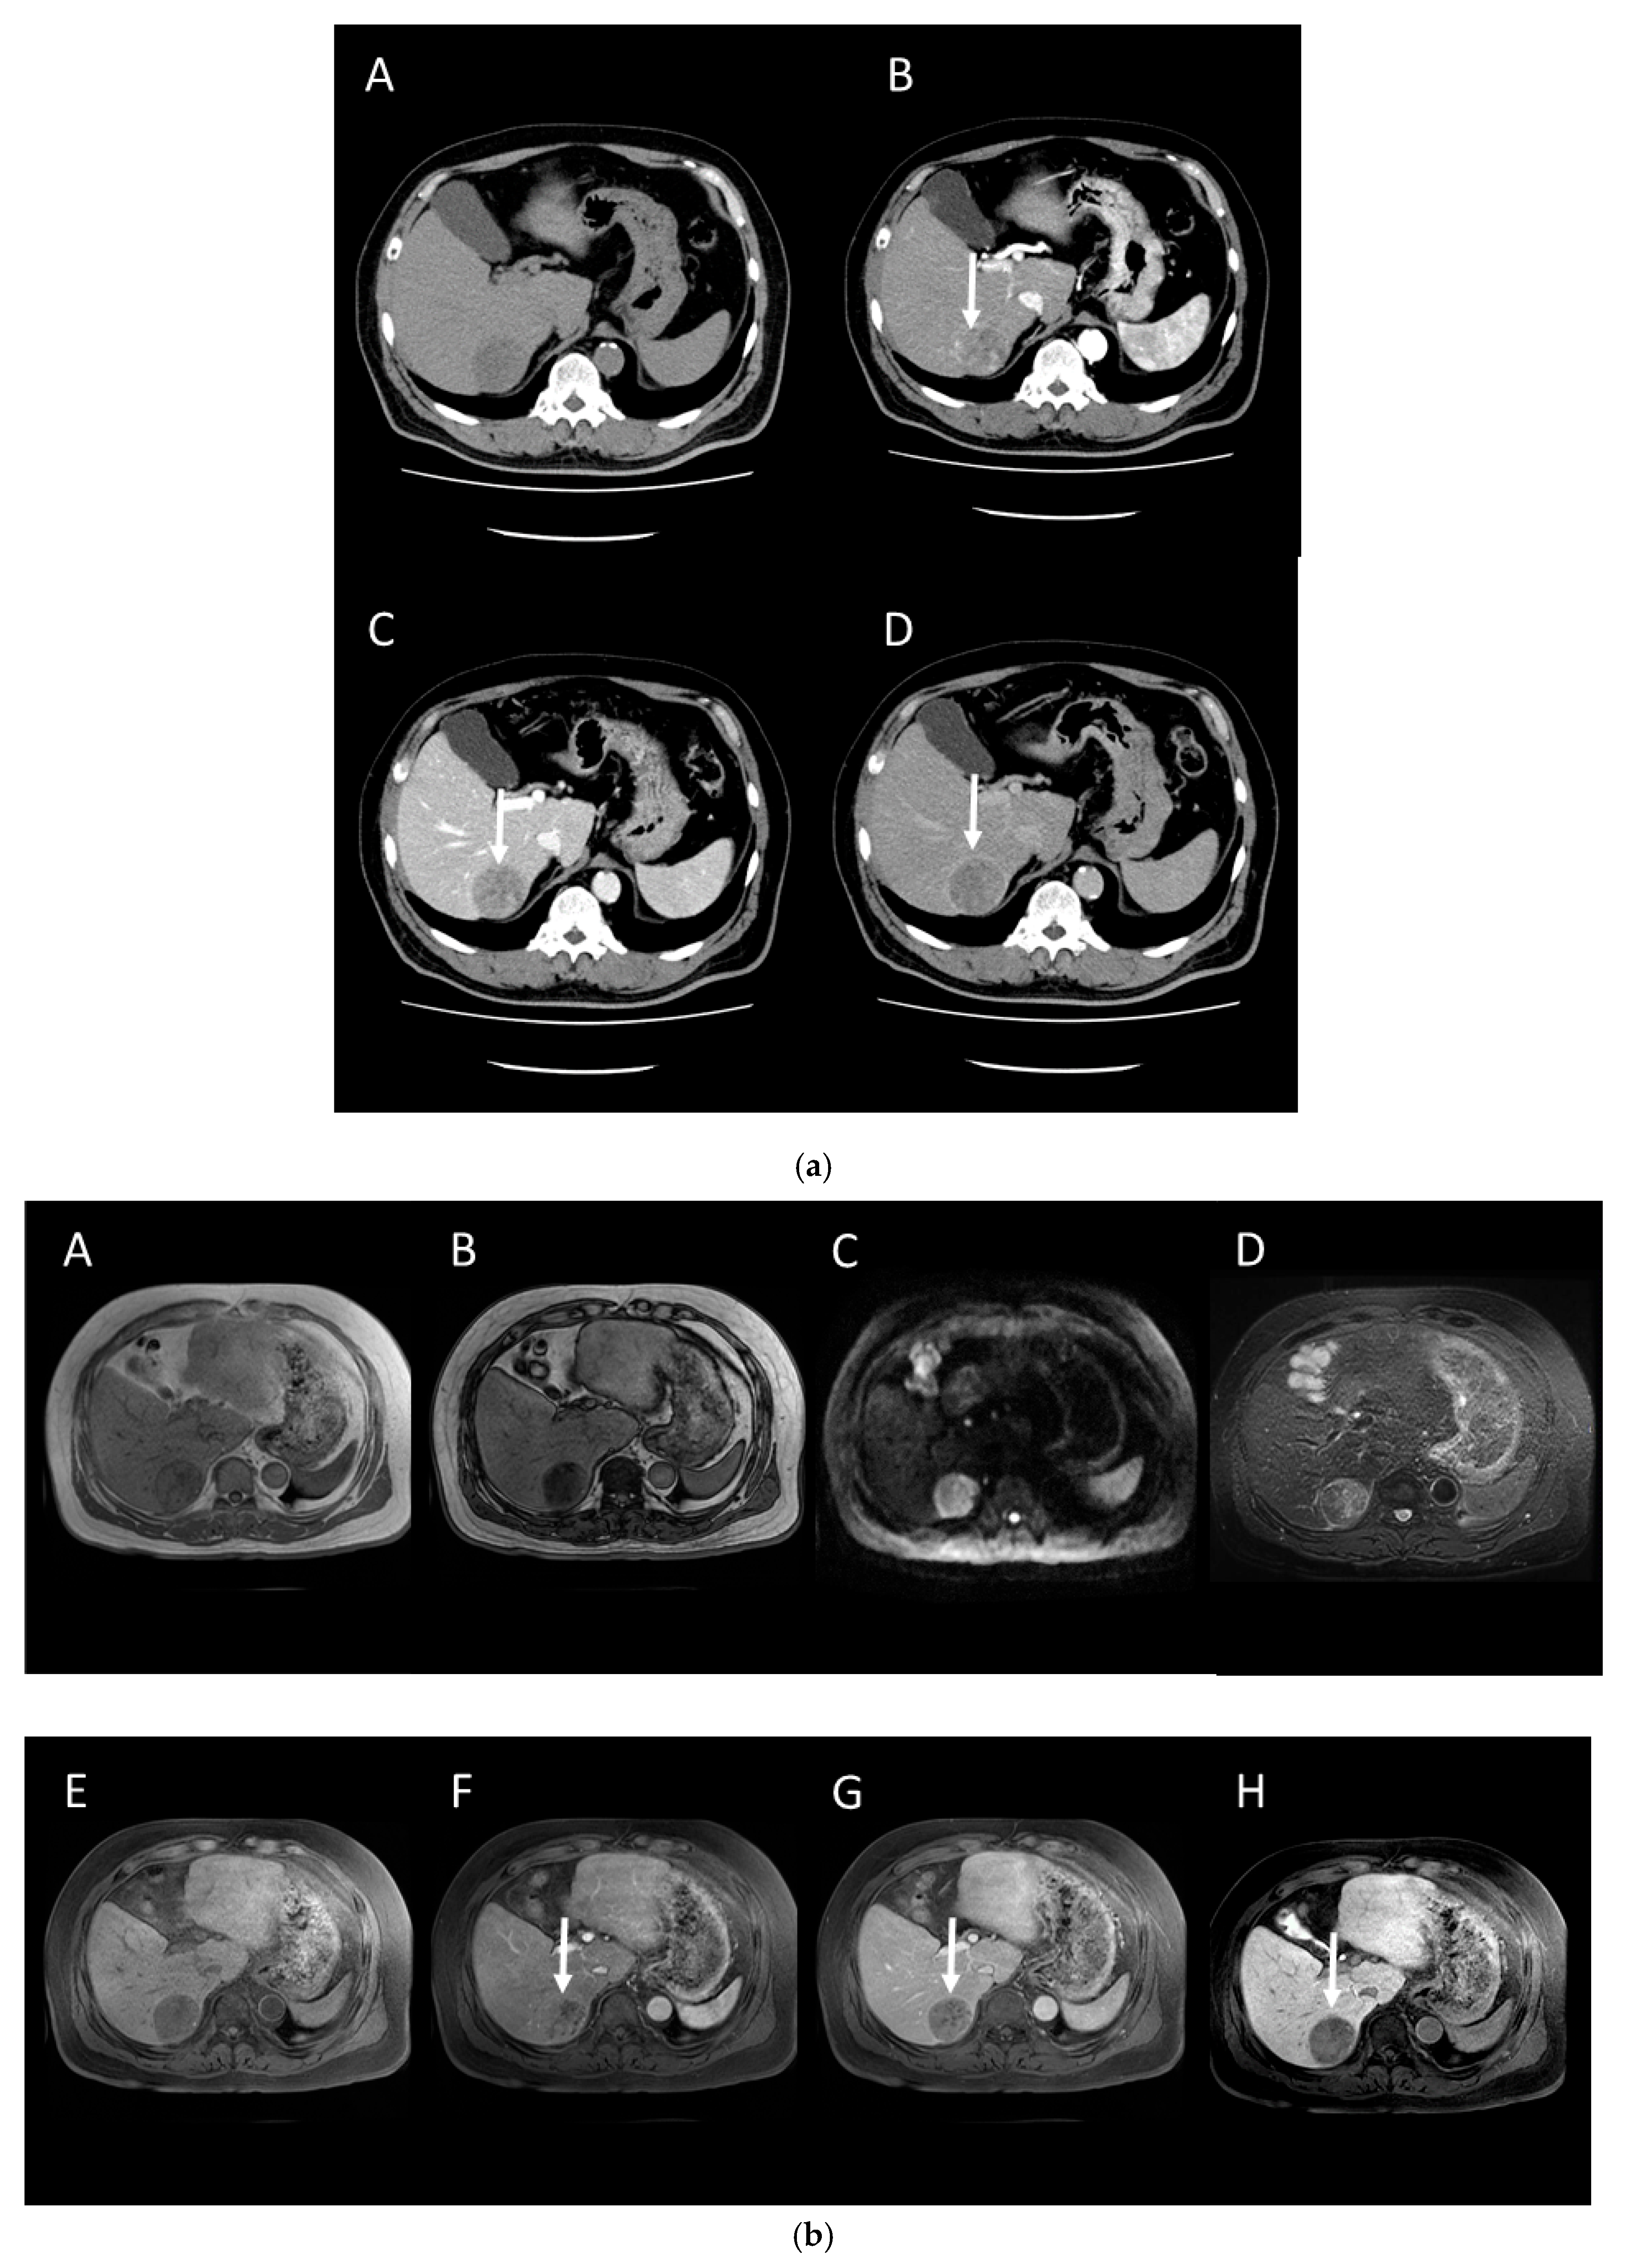

4.2. Early Hepatocellular Carcinoma (Early-HCC)

4.3. Well-Differentiated Hepatocellular Carcinoma (Well-HCC)